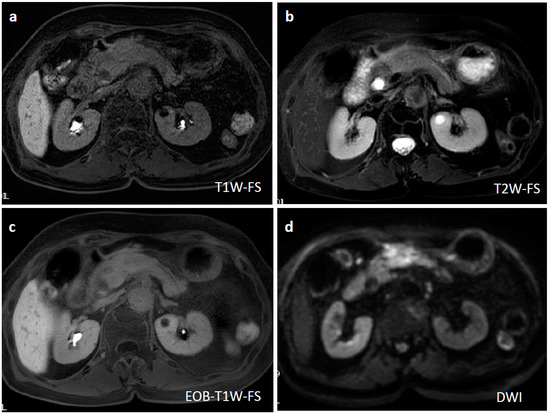

Figure 6.

Magnetic resonance imaging (MRI) at two weeks after EUS-FNAB and three weeks after the initial CT. A T1-weighted MRI showed an iso-intensity signal (a), a T2-weighted image showed a faint low-intensity signal (b), a gadoxetate sodium-injected MRI demonstrated a slightly weak enhancement (c), and a diffusion-weighted MRI revealed heterogeneously repressed diffusion ability at the pancreatic lesion (d).

Ten days after FNAB, positron emission tomography showed abnormal 18F-fluorodeoxyglucose uptake (SUVmax: 6.95); however, the pancreatic lesion seemed to have shrunk to 2.5 cm in size (Figure 5). Magnetic resonance imaging (MRI) demonstrated an obviously minimized tumorous lesion at the pancreas head (Figure 6). The mass lesion was visible as an iso-intensity signal in a T1-weighted image and as a faintly low-intensity signal in a T2-weighted image, while it was ill enhanced in an EOB image and the signal was heterogeneously repressed in a diffusion-weighted image. A subsequent CT, conducted one month after the FNAB, revealed further minimization of the pancreatic mass (Figure 1c,d). The images obtained in the next two months showed that the tumor had almost vanished. The tumor was no longer visible at the sixth month. During the post-diagnosis course, no medication was administered other than regularly taken hypotensive drugs. A written informed consent was obtained from the patient.